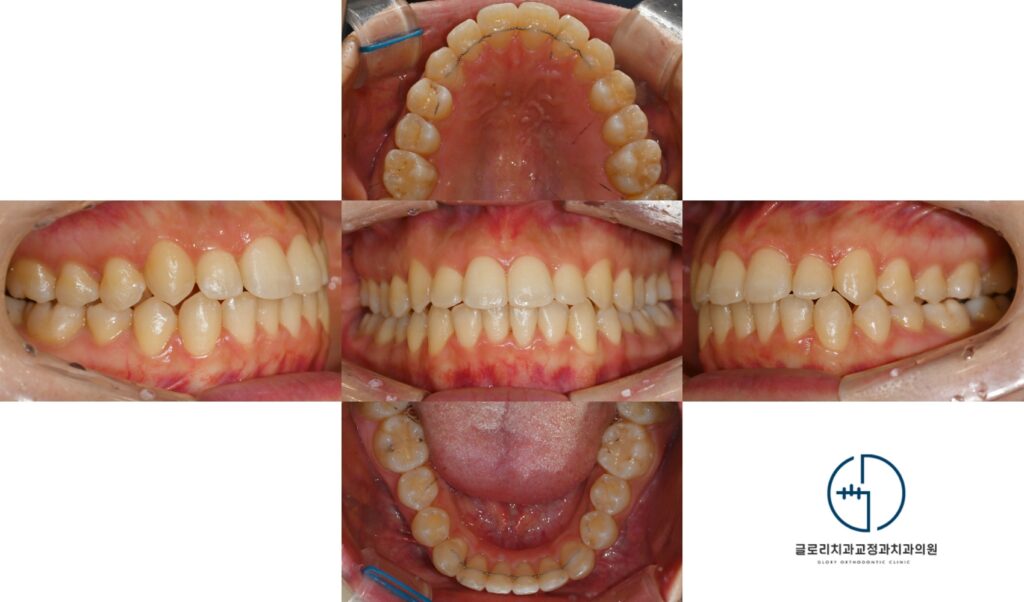

상봉동 교정치과 에서 준비한 구강사진을 보면 현재 앞니가 서로 겹쳐 배열되어있으며 치열이 전반적으로 고르지

못한 것을 알 수 있습니다. 이처럼 공간부족으로 인해 치아들이 서로 겹쳐있는현상을 총생, 덧니라고도 칭합니다.

예시 사진을 보면 현재 치면에 하얗게 부착되어있는 재료가 보입니다.

이는 인비절라인 과정에서 사용되는 어태치먼트로 투명장치가 자연치를 정밀하게 잡아주고

계획된 방향으로 힘을 전달할 수록 돕는 역할을 합니다.

특히나 회전이 필요한 치아나 경사 이동이 요구되는 전치에서는 어태치먼트의 위치와 형태가 그 결과에 큰 영향을 미치게 됩니다.

단계별 교체과정을 통해 불규칙했던 치열이 개선되고 모든 치료가 마무리된 구강을

살펴보겠습니다. 겹쳐있던 앞니는 자연스럽게 정렬되었으며 과도한 전방경사

없이 안정한 교합 관계가 형성되었습니다.

웃을때 역시 드러나는 치열선이 정돈되었고 전반적인 심미성이 높아진 것을 확인할 수 있습니다.